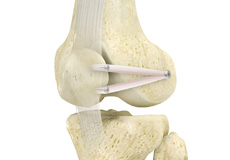

Fractures of the Patella

The patella or kneecap is a small bone present in the front of your knee where the thigh bone meets the shinbone. It provides protection to your knee and attachment to muscles in the front of the thigh.